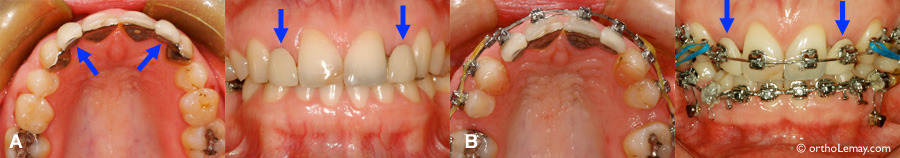

Restaurations dentaires en amalgame sur plusieurs dents postérieures

(A) Restaurations dentaires en amalgame sur plusieurs dents postérieures. (B) Ces restaurations ont été remplacées par du composite avant le début des corrections orthodontiques afin d’éliminer plusieurs obturations défectueuses.